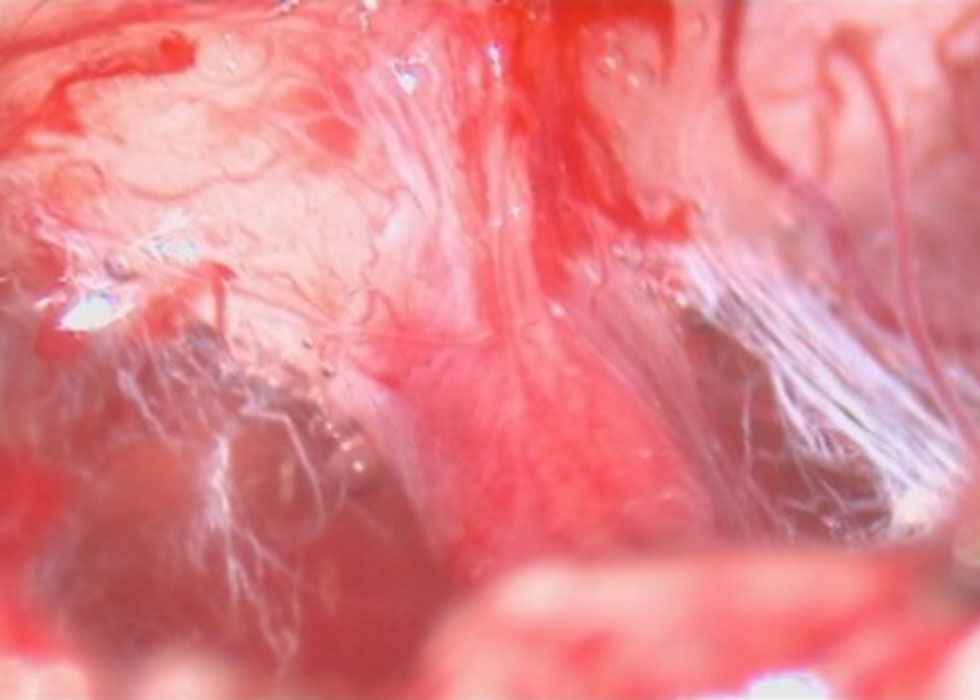

術中写真

摘出 中